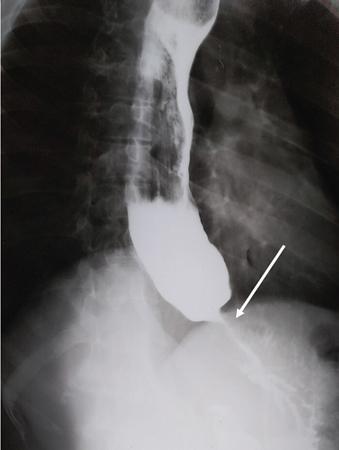

Single contrast barium study (Fig. 7.4.5.1), CECT (Figs. 7.4.5.2 and 7.4.5.3).

Image

Fig 7.4.5.1 Barium study of the patient.

Observations

Barium study shows large filling defect in the antrum forming acute angles with the wall. Undulating contour is seen along greater curvature with ulceration of overlying mucosal irregularity.

CECT shows a large lobulated mass involving lesser curvature and antrum with marked wall thickening along distal greater curvature.

Diagnosis

Carcinoma stomach.